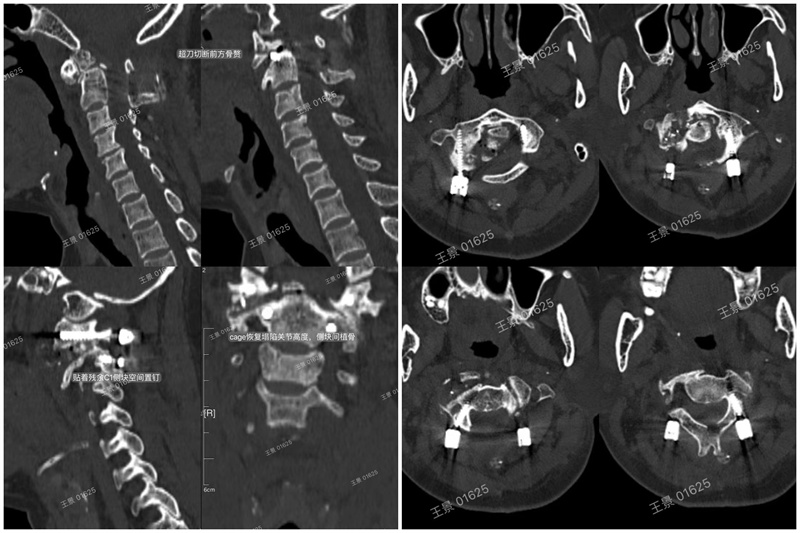

术中资料

术后影像资料